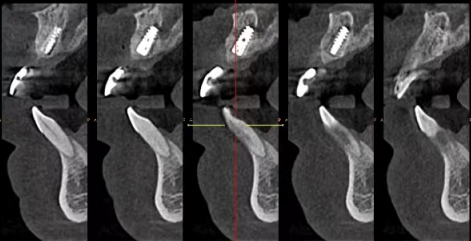

此外,种牙的部位、手术的复杂程度等也会对拆线时间产生一定影响。比如,后牙区的种牙手术相对复杂,伤口可能较大,愈合时间可能会稍长一些;而前牙区手术相对简单,伤口较小,愈合可能会快一点。